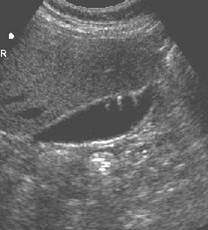

Tumefactive sludge

Sludge